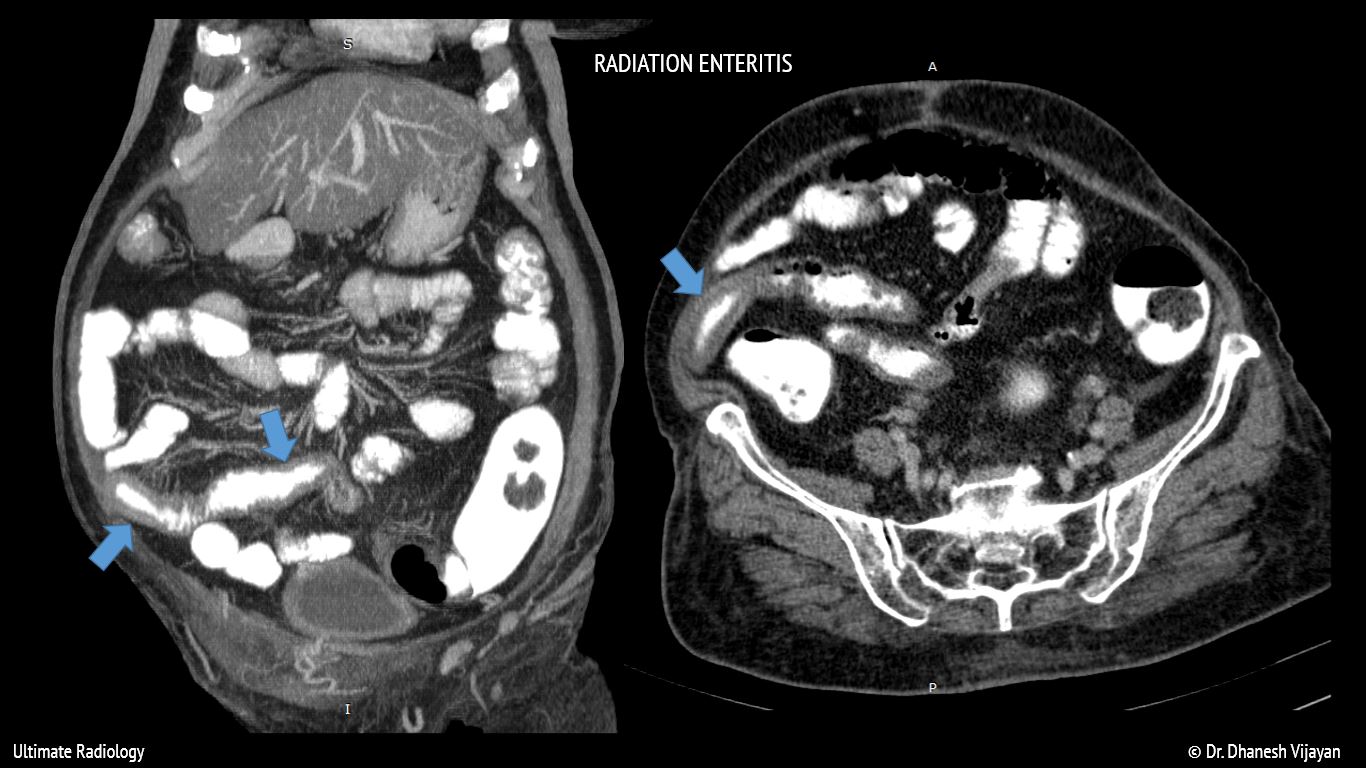

Ultimate Radiology Radiation enteritis Radiation Enteritis Ppt Radiation therapy is frequently used in many types of cancer, including anal, cervical, prostate, and rectal. An awareness of the patient’s radiation history and knowledge of the clinical signs and symptoms of the phases of radiation. The term radiation enteritis describes the inflammatory and degenerative changes seen within the small intestine after. Acute radiation enteritis is exceedingly common; This review. Radiation Enteritis Ppt.